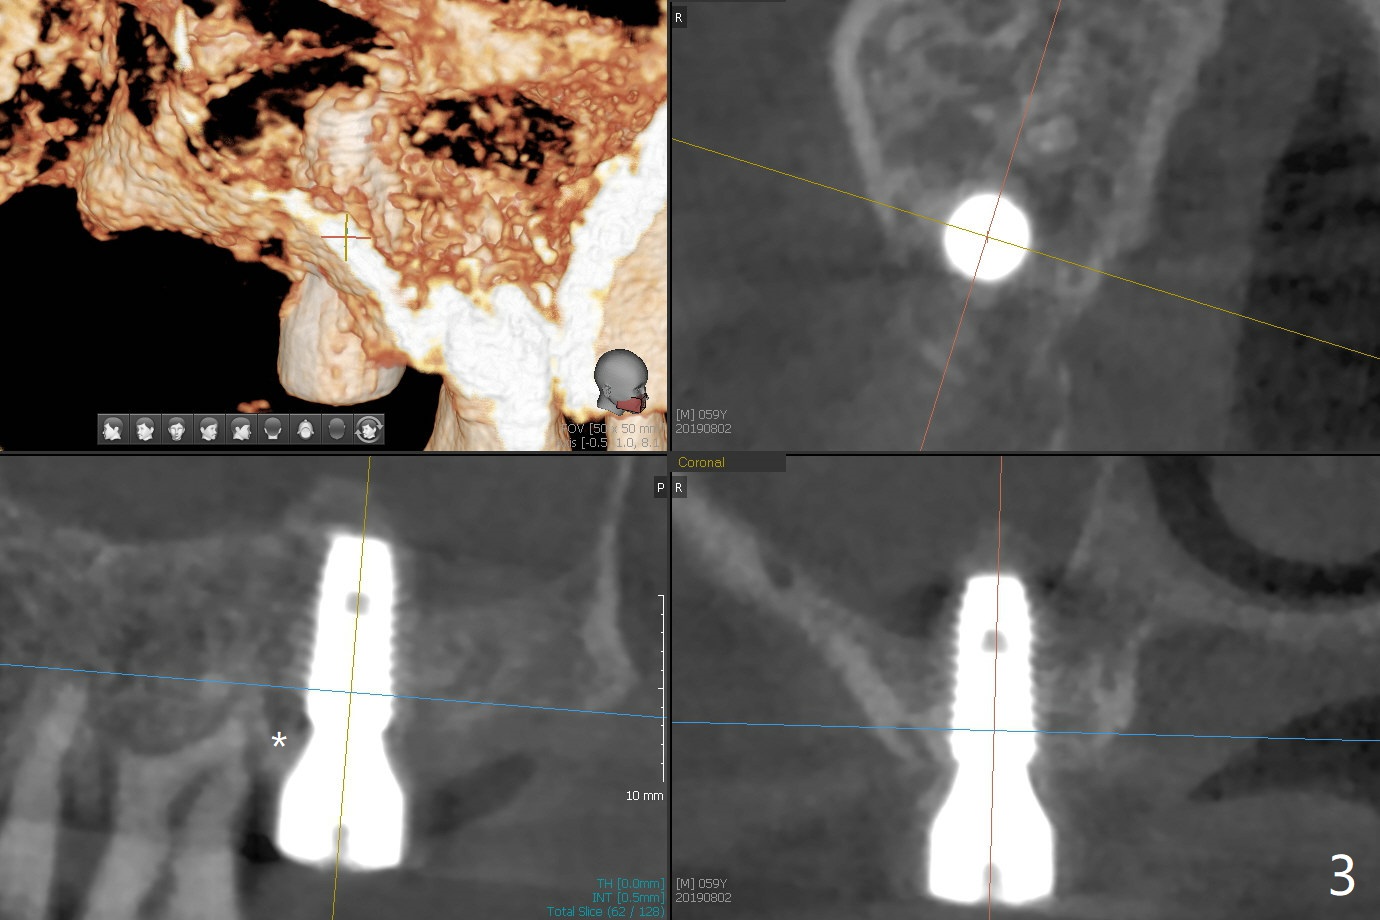

Two things happen immediately before this surgery. A SM implant is found to fail related to bruxism and poor oral hygiene, ~ 5 years in function; a UF implant will be used instead. DIO Sinus Approach Kit has not been autoclaved; therefore the free-hand one has to be used with caution. In fact the procedure goes on apparently smoothly in spite of the fact that the patient with medical knowledge is nervous about the risk of sinus lift. After 4.0x8.5 mm Neo Navi drill with 12 mm offset, the 3.6 mm sinus safety drill is used from 7 to 9 mm in length, followed by water balloon, PRF membranes (x2) and mixture of autogenous bone graft and allograft and 4.5x10 mm dummy implant (Fig.1). The definitive implant is placed with satisfactory stability (Fig.2), but a 6.5x7(4) mm healing abutment is close to the mesial crest (*). The former is reloaded following 6.0 mm Bone Profile Drill (Fig.3) and then is changed to a 6x6 mm IS one. The patient reports nasal hemorrhage immediately returning home, but there is no similar episode a few hours later. Re-analysis of preop (Fig.4) and immediate postop (Fig.5) CT shows that water balloon technique in fact swells the sinus membrane (M) instead elevating it. It is safe to place more bone graft (Fig.5 *). There is pain when the 6x6 mm healing abutment is being removed nearly 5 months postop (Fig.6.7). The patient complains of mild sinus discomfort, although panoramic X-ray does not show abnormality (Fig.8). He will return for recheck for implant stability (low bone density) before impression 2-4 months later.